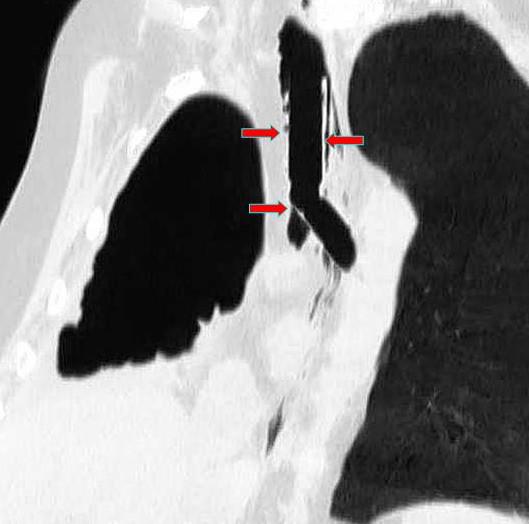

We describe a case of late bronchopleural fistula after right extrapleural pneumonectomy for malignant mesothelioma. Bronchoscopic attempts to repair it were unsuccessful.

The use of a modified Y Dumon stent associated with glue apposition on the bronchial stump allowed us to close the fistula without the need of any surgical repair.

我们描述了一例因恶性间皮瘤行右胸膜外全肺切除术后发生迟发性支气管胸膜瘘的病例。支气管镜下修复尝试未成功。

使用改良的Y型杜蒙支架并在支气管残端涂抹胶水,使我们无需进行任何手术修复即可闭合瘘口。